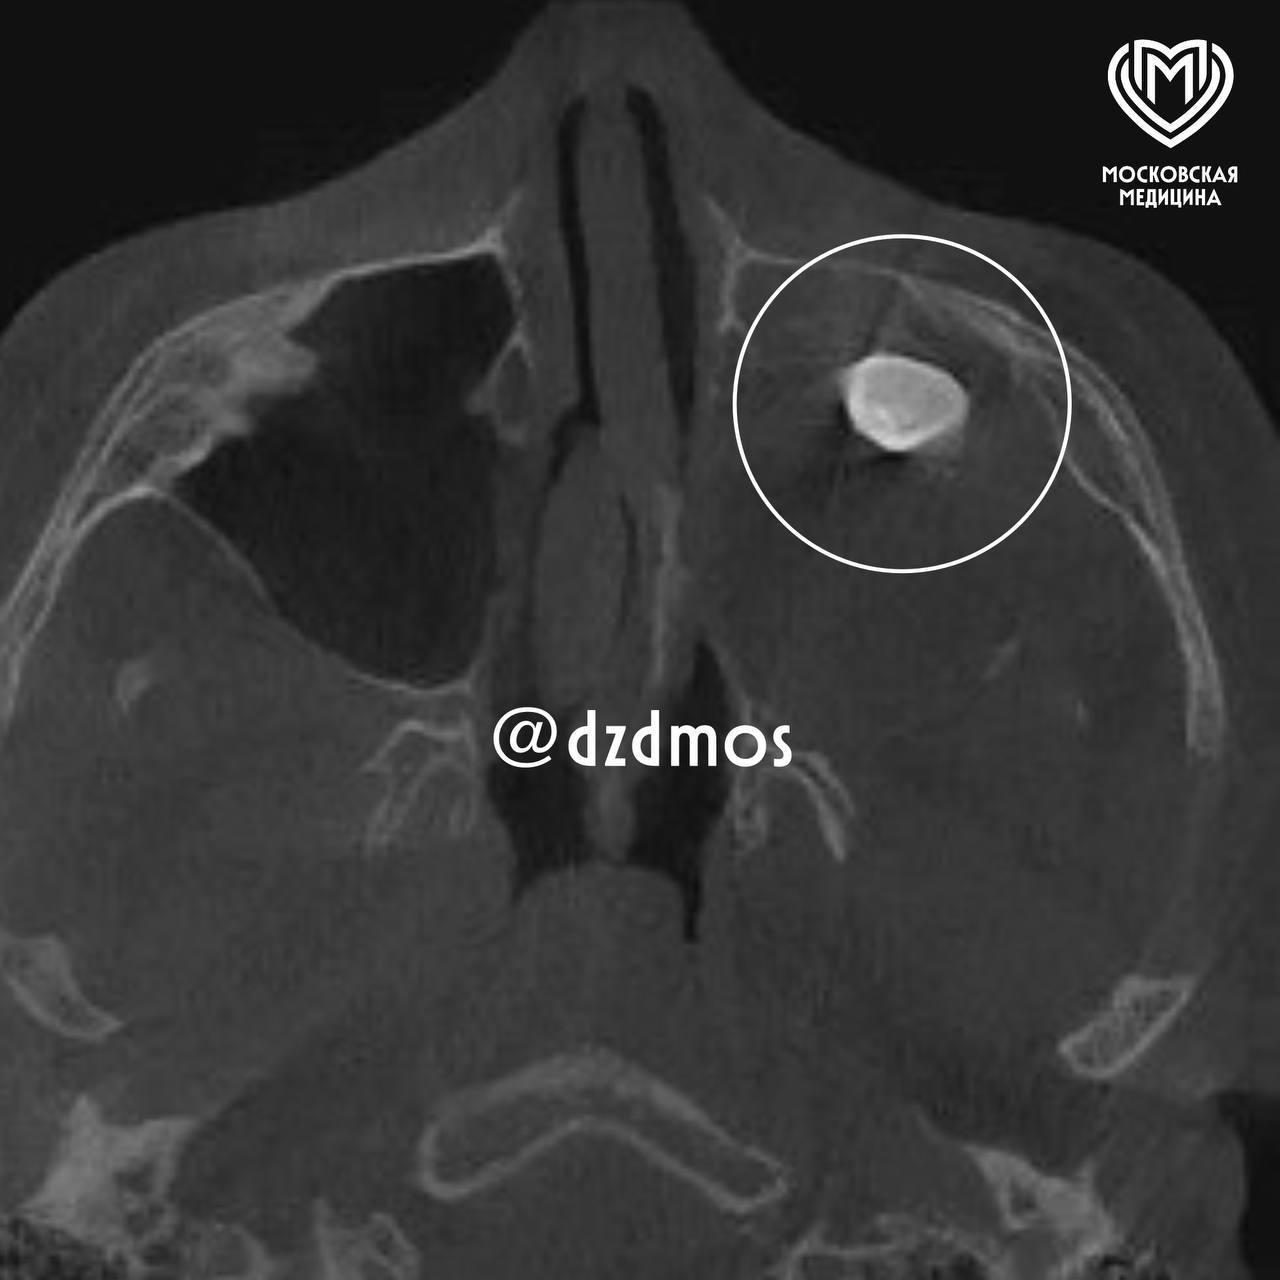

Московские врачи удалили подростку выросший в носу зуб, сообщает столичный департамента здравоохранения.

Во время операции врачи обнаружили новообразование, внутри которого и находился зуб. Позже выяснилось, что это доброкачественная тератома.